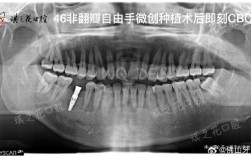

术前检查与设计(1-2周)

通过口腔CT、曲面断层片、模型扫描等数据,结合咬合关系、面部美学比例,设计种植体植入位置、角度及深度,数字化导板技术的应用,能让手术误差控制在0.1mm以内,尤其适合对美观要求高的前牙区种植。